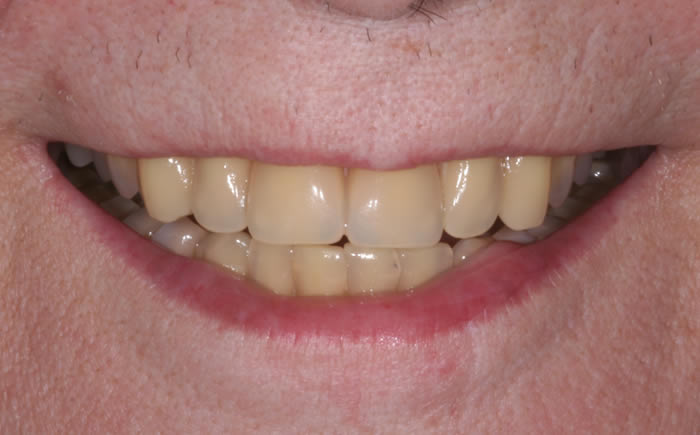

Gum disease

Case One (2 images)

Treatment of severe gum disease.

Case Two (2 images)

Treatment of moderate gum disease.

Case Three (2 images)